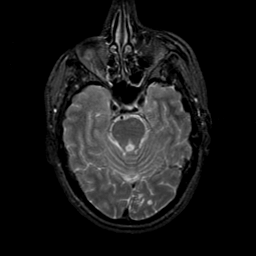

MR Study #23, January 26, 1992 -- Slice #16